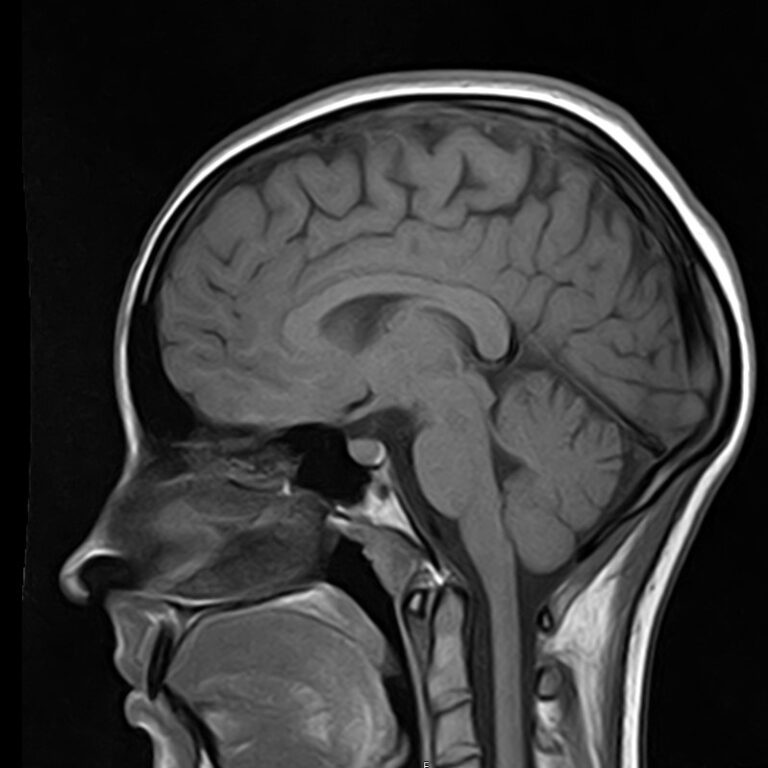

Сканирование проводится на современном высокопольном магнитно-резонансном томографе закрытого типа TOSHIBA VANTAGE TITAN 1,5 Тесла, который делает послойные срезы в разных плоскостях с шагом от 1 мм и на основе полученных данных создает трехмерные изображения превосходного качества. Метод исследования позволяет в мельчайших подробностях визуализировать состояние всех структур головного мозга и шейного отдела позвоночника, что дает возможность выявлять патологические изменения на ранних стадиях и назначать своевременное лечение.